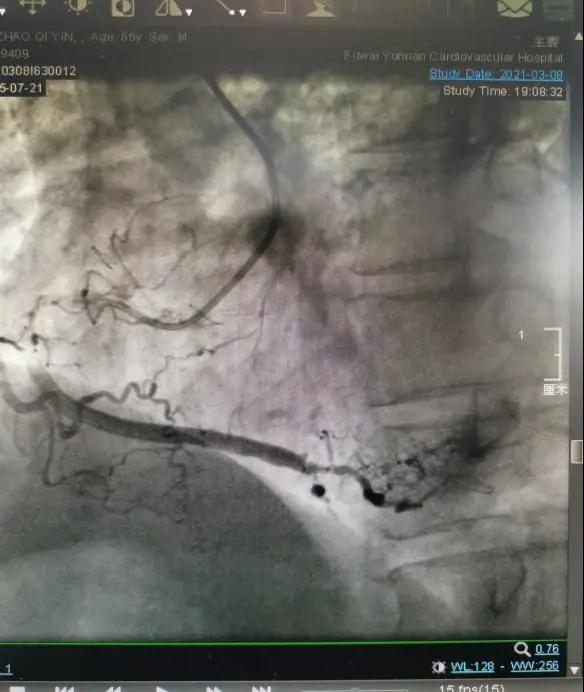

患者多次在外院就诊,冠脉造影检查明确其冠脉血管已经严重钙化,尝试使用药物球囊等技术,术后患者仍发作胸闷胸痛,持续无法缓解,辗转来到云南省阜外医院求诊,入院后收入ICU治疗。冠脉造影显示:患者左、右冠状动脉血管近端严重钙化斑块,远段闭塞,是真正的命悬一线。

病情危重,冠脉病变复杂,齐峰教授勇挑重担,率团队仔细询问病史和阅读冠脉影像,讨论后决定采用冠脉准分子激光斑块消融的方法,来解决患者冠状动脉病变。术中在左冠状动脉反复行激光消蚀术8次后于前降支近中段顺序植入2枚支架。重新疏通了“心路”,患者术后观察了2天无不适症状,顺利出院回家。